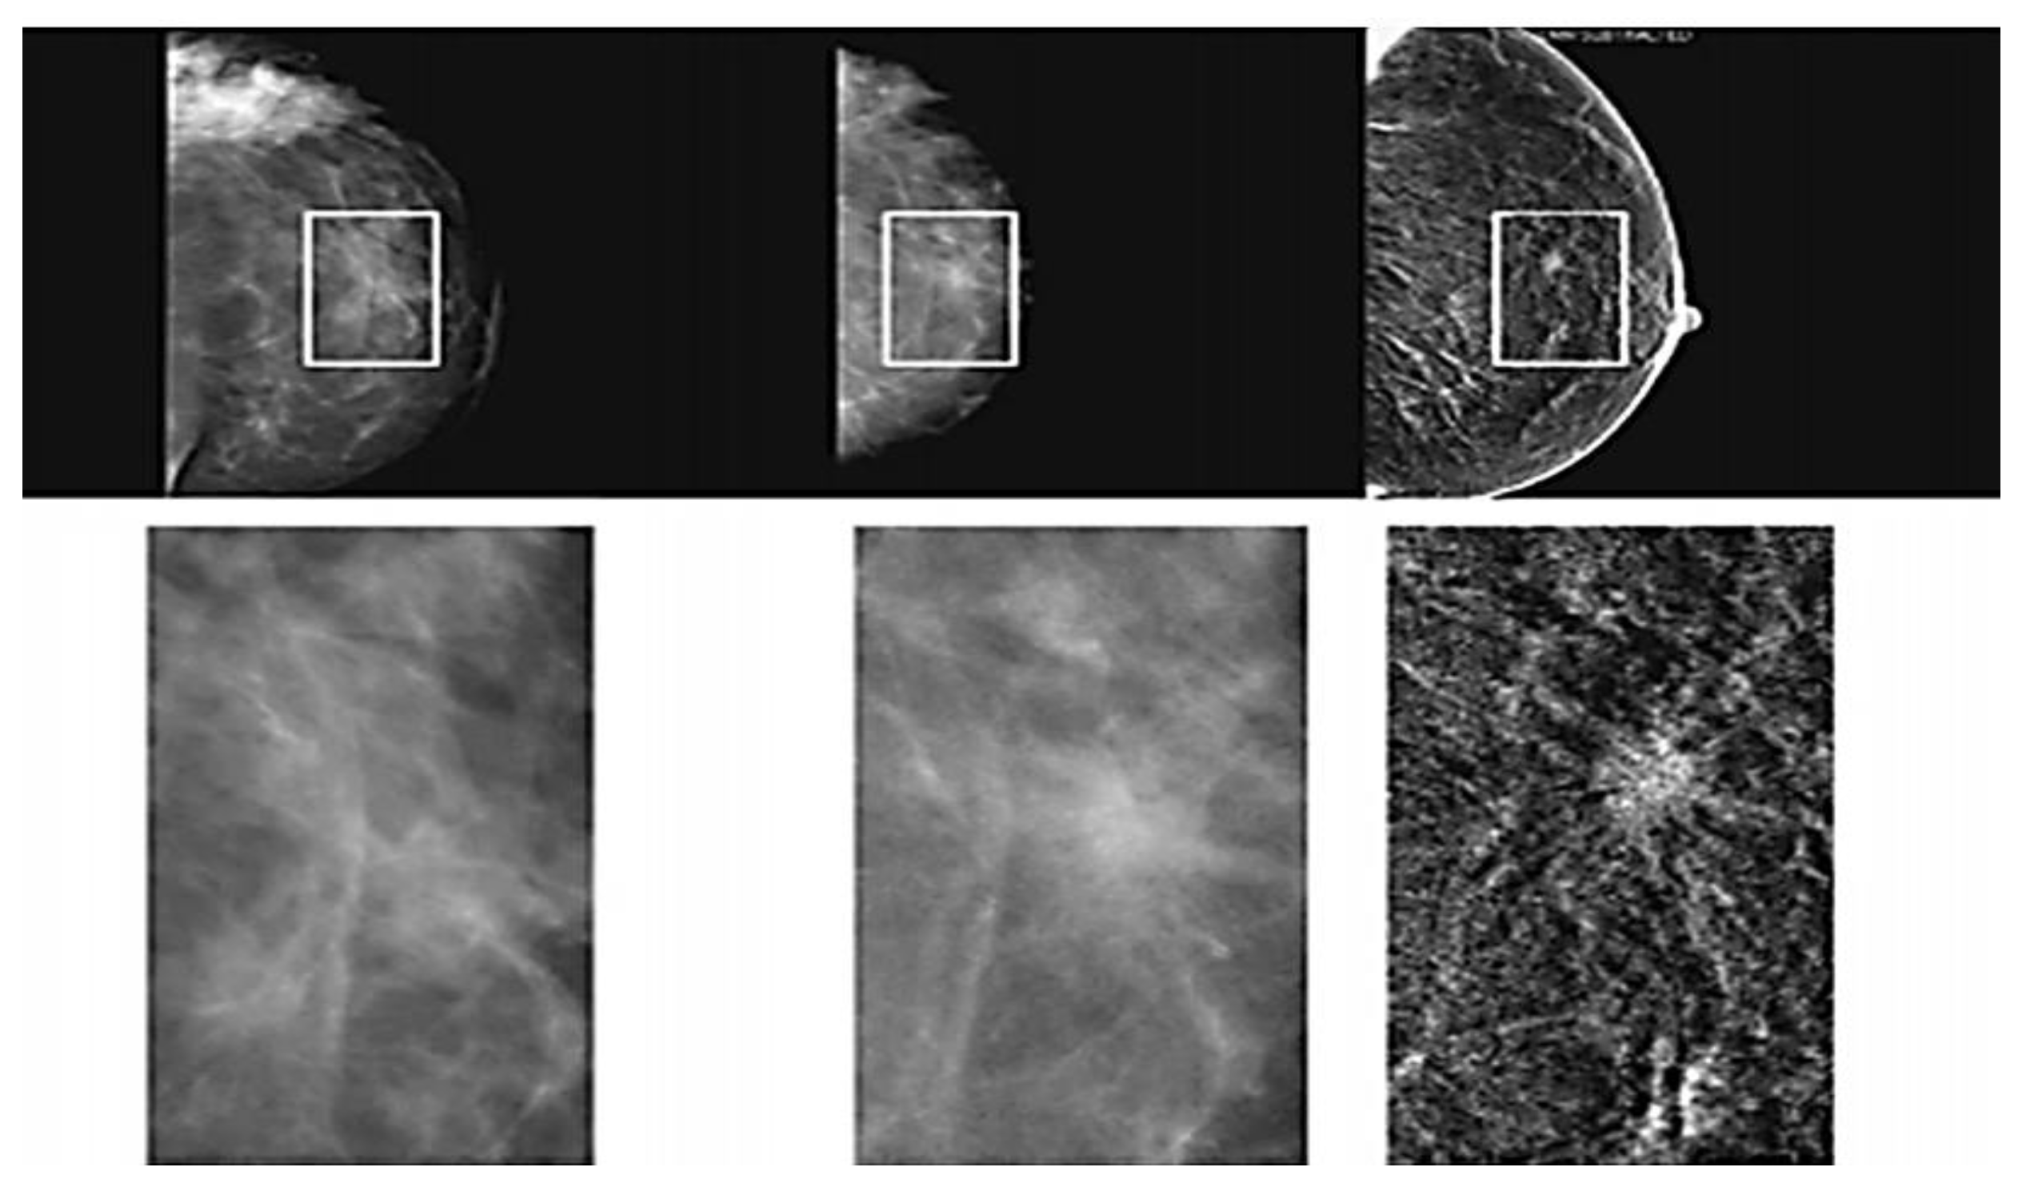

2.1.3. Magnetic Resonance Imaging (MRI)

- Kamal, R.; Mansour, S.; Farouk, A. Contrast-enhanced mammography in comparison with dynamic contrast-enhanced MRI: Which modality is appropriate for whom? Egypt. J. Radiol. Nucl. Med. 2021, 52, 216. [Google Scholar] [CrossRef]

- Iranmakani, S.; Mortezazadeh, T.; Sajadian, F.; Ghaziani, M.F.; Ghafari, A.; Khezerloo, D. A review of various modalities in breast imaging: Technical aspects and clinical outcomes. Egypt. J. Radiol. Nucl. Med. 2020, 51, 57. [Google Scholar] [CrossRef]

- Mann, R.M.; Kuhl, C.K.; Moy, L. Contrast-enhanced MRI for breast cancer screening. J. Mag. Resonance Imaging 2019, 50, 377–390. [Google Scholar] [CrossRef]

- Mann, R.M.; Cho, N.; Moy, L. Breast MRI: State of the Art. Radiology 2019, 292, 520–536. [Google Scholar] [CrossRef]